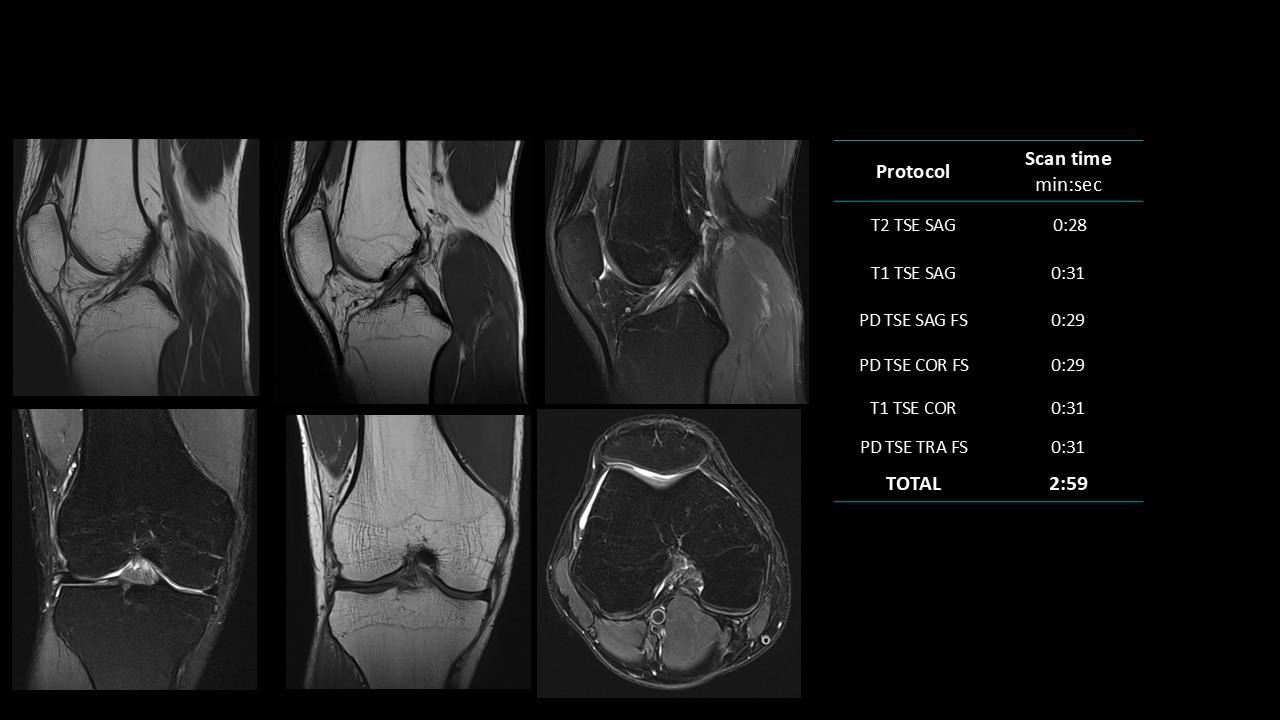

The Deep Resolve protocols are a set of advanced 3T MR imaging protocols designed to achieve high-quality diagnostic imaging with significantly reduced acquisition times.

Enabled by Deep Resolve, the AI-powered image reconstruction technology, these protocols deliver high-quality scans in approximately three minutes across a wide range of anatomical regions.

Developed and meticulously evaluated by Dr. Seong-ho Lee of Leaders Radiology Hospital in Seoul, Korea, the protocols integrate deep learning technology to enhance imaging efficiency while maintaining diagnostic detail.

By reducing scan duration, they improve workflow efficiency and patient experience without compromising image quality.